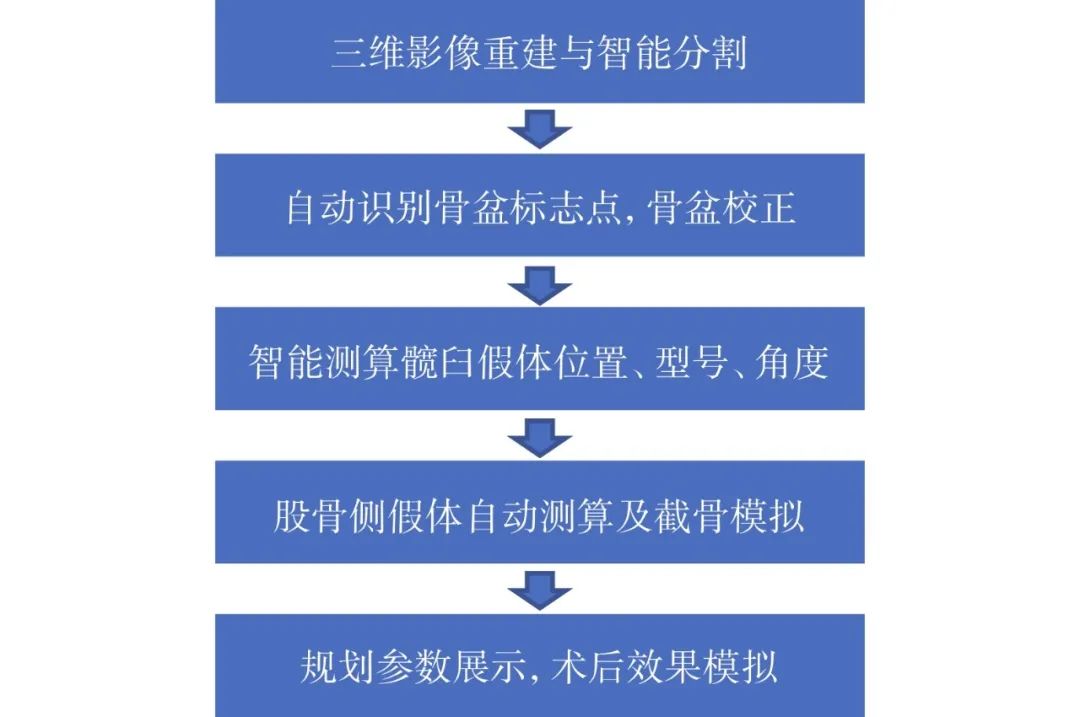

1.2.1 智能规划髋臼侧 AIHIP 系统采用独创的G-NET 神经网络技术(图 2),通过融合 Unet 结构、DenseBlock 结构、LSTM 网络和 PointRend 技术,可以精准识别骨骼边缘并进行精确分割(图3a)。接着在骨盆分割基础上对髋臼进行拟合,进而计算髋臼的旋转中心以及半径;再结合骨盆矫正结果(图 3b、c),规划出髋臼杯合适位置(图3d~h)。

图 2 AIHIP 系统自研独特算法(G-NET 神经网络)骨骼分割示意图

第一,AIHIP 系统提高临床工作效率。神经网络是一种模仿动物神经网络行为特征,进行分布式并行信息处理的算法数学模型。AIHIP 软件可以借助其独特的 G-NET 神经网络技术,快速识别解剖位点并分割,匹配所需假体的型号、大小,规划旋转中心、股骨距保留长度,高效实现术前规划。相比目前较为流行的 3D 打印辅助 THA 术前规划[18],其处理速度快是明显优势。此外,其他现有的三维术前规划软件存在操作繁琐、需要手动标记、耗时较长、价格昂贵等不足[14]。在识别速度方面,同类三维术前规划软件,如 Mimics、HipPlan 等,因需要手动分割,每例规划用时约 24 min;AIHIP 系统每例规划用时平均约 5 min,明显精简、缩短了术前规划时间。

第二,AIHIP 系统准确率较高。国内 THA 术前规划仍以传统基于二维 X 线片测量为主,因放大率不准确、拍摄投照角度存在差异、操作繁琐、假体型号种类不全等问题,术前规划常不准确,严重影响 THA 手术效果[10-12]。而且 Crowe Ⅳ型 DDH 患者髋关节高脱位、双下肢真性不等长、髋关节外翻,因此周密的术前计划非常重要。AIHIP 系统利用自研的 G-NET 算法,基于 Unet 结构、Dense-Block 结构、LSTM 网络、PointRend 技术对骨骼骨块进行精准分割并识别关键解剖点,平均识别误差为 0.87 个像素值,骰子重叠系数精度为 92.5%,高于传统分割网络,且具有更好的鲁棒性(robust-ness)。在假体放置方面,该系统将监督学习和基于强化学习的无监督学习相结合,依据假体设计理念及人体解剖结构,智能放置假体位置,计算最适角度,假体完全匹配率可达 90% 以上。既往二维规划相关研究发现,髋臼杯符合率为 7.3%~70%,股骨干符合率为 36%~79%[18-19]。本研究中 AIHIP 系统规划假体型号的符合率高于传统二维规划。